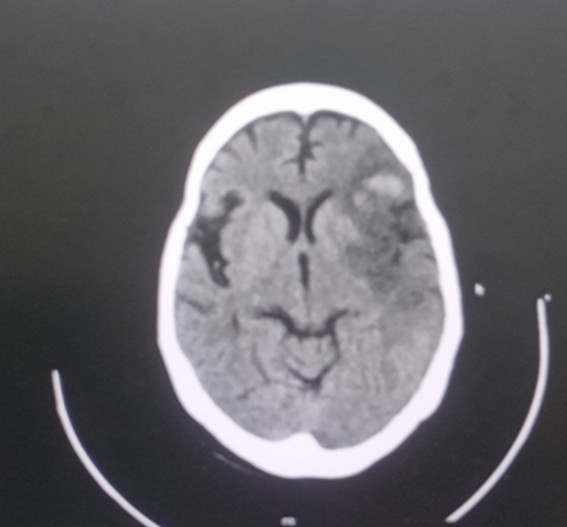

CT brain – 20.2.25

Acute non-hemorrhagic infract in left MCA territory

Age related Atrophy

CT brain – 21/2/25

Sub-Acute infract in left MCA territory infract with grade 2 hemorrhagic transformation mass effect with no significant midline shift